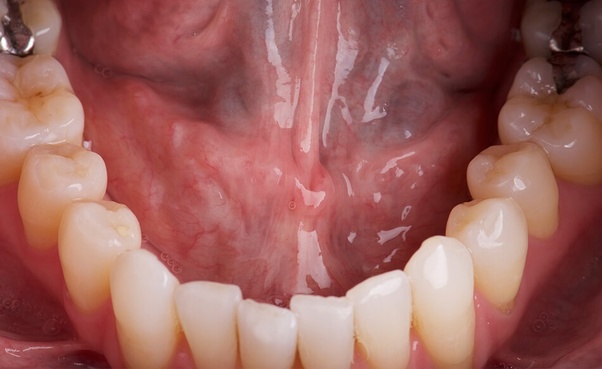

Skin Cancer Quora / What is mouth cancer? What are the symptoms and treatment for it? - Quora. Spots on the skin that won't go away easily. Other signs of cancer might be a bloated belly, nausea, weight loss, and bleeding when you go to the bathroom. With detailed neem oil uses for health, skin, acne, face, hear, beauty, plants and garden. 02.12.2021 · melanoma is a type of skin cancer. Black spots on skin std